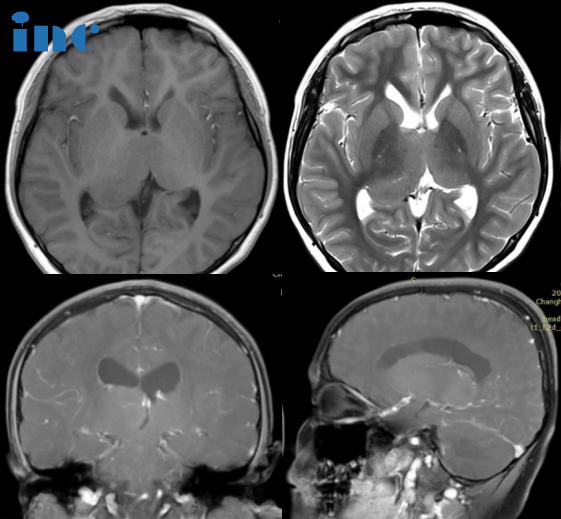

病史摘要:2022年4月1日,涛涛因头部受伤进行头颅CT检查,结果是头部有钙化灶。7月15日,父母带涛涛到医院查头颅MRI平扫+增强,诊断结果是双侧丘脑胶质瘤可能。7月26日,再次到医院查头颅MR波谱成像(MRS),诊断结果是右侧丘脑恶性肿瘤。随后又到北京某医院问诊说可以手术,但是无法全切,且手术风险很大。涛涛目前还没有明显的症状,只是偶尔在走路的时候会突然绊一下。如果手术后,孩子变得比现在状态更差,涛涛父母犹豫了。手术还是不手术,他们多方打听之下,决定咨询国际颅底脑干手术教授巴特朗菲教授,想要听听他的意见。

INC巴教授远程评估意见:

对比2022年和的影像,我监测不到肿瘤有任何生长,很明显这是一个钙化的低级别胶质瘤。CT扫描很好地显示了右侧肿瘤内的强化的钙化。

在这种情况下,特别是考虑到这个男孩的临床状况良好,我们可以通过反复的核磁共振成像检查对他的病例进行跟踪,因此,如果出现任何变化,我们都可以很容易地发现。

不过,这种肿瘤很有可能在多年内保持稳定,而且,在接下来的几年里,当男孩继续生长时,肿瘤甚至可能出现退化(肿瘤体积可以在不治疗的情况下缩小)。当然,这只是一种可能性,我们当然不能确定这种有利的发展过程是否真的会发生,但至少有很大的机会出现这种有利的情况。

至于体重增加,也许是因为下丘脑也受累了,因为下丘脑与丘脑紧密相连,也许也含有小部分肿瘤。因此,男孩需接受儿科肿瘤专家的诊治,检查全部(下丘脑相关的)激素,并根据具体情况替代激素。不过,要阻止下丘脑肿瘤引起的体重增加并不容易,因为目前还没有合适的药物。